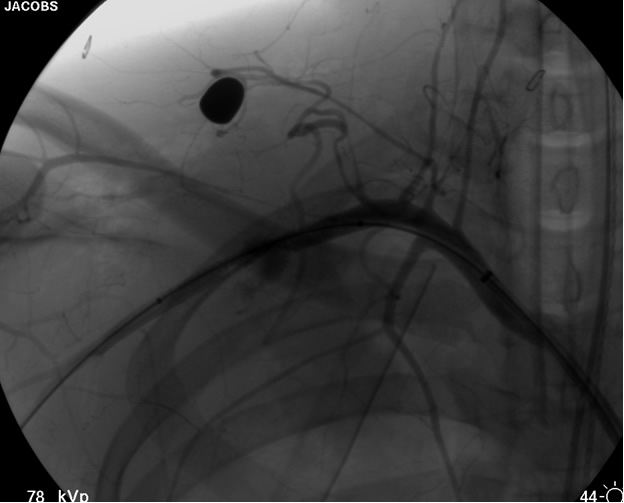

transected artery visualizing the pseudoaneurysm (Figure 2). A Viabahn covered stent (W.L. Gore & Associates, Flagstaff, AZ) is chosen for the appropriate size of the native vessel being careful not to oversize the stent graft. The stent graft is advanced across the lesion. Selective angiograms through the sheath may be performed to choose correct placement and appropriate landing zones. The stent graft is deployed under fluoroscopic visualization. Next, we utilize an appropriate sized 10 mm low pressure balloon to “iron out the edges” of the stent and bring it up to profile of the artery (Figure 3). Next, completion angiograms are performed to rule out endoleak and complete exclusion of the pseudoaneurysm, as well as to confirm distal runoff to the forearm and palmar branches of the extremity (Figure 4).

![]() |

| Figure 4: Post-deployment of the stent with 10 mm balloon brought up to vessel profile. |